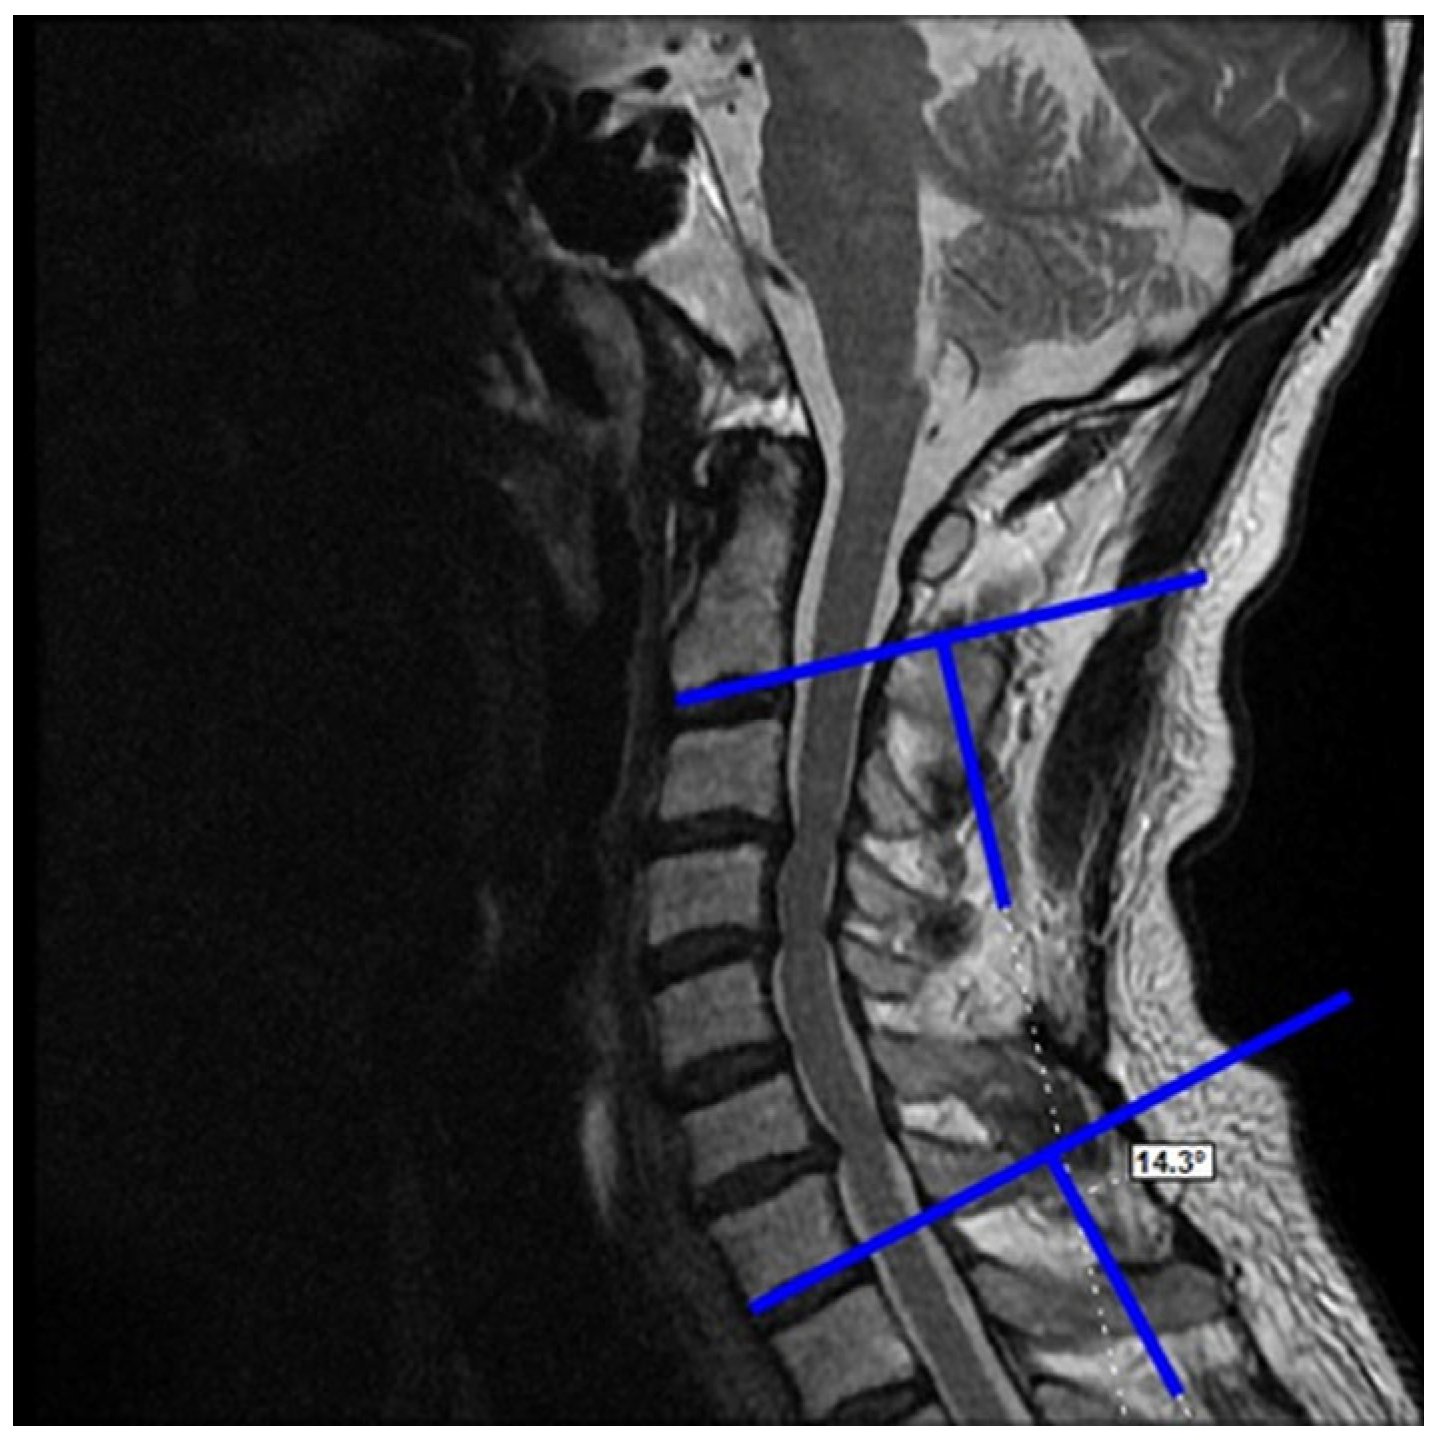

2.3. Dependent Variables (Radiological)

- Postoperative last control C2–C7 Cobb angle

- Postoperative last control cervical alignment

- Postoperative last control K-line